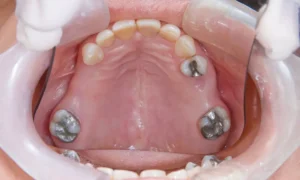

Should You Replace Old Silver (Amalgam) Fillings with White Composites?

Dental health is one aspect of personal care that deserves constant attention. One common dilemma many encounter is whether they should replace their old silver